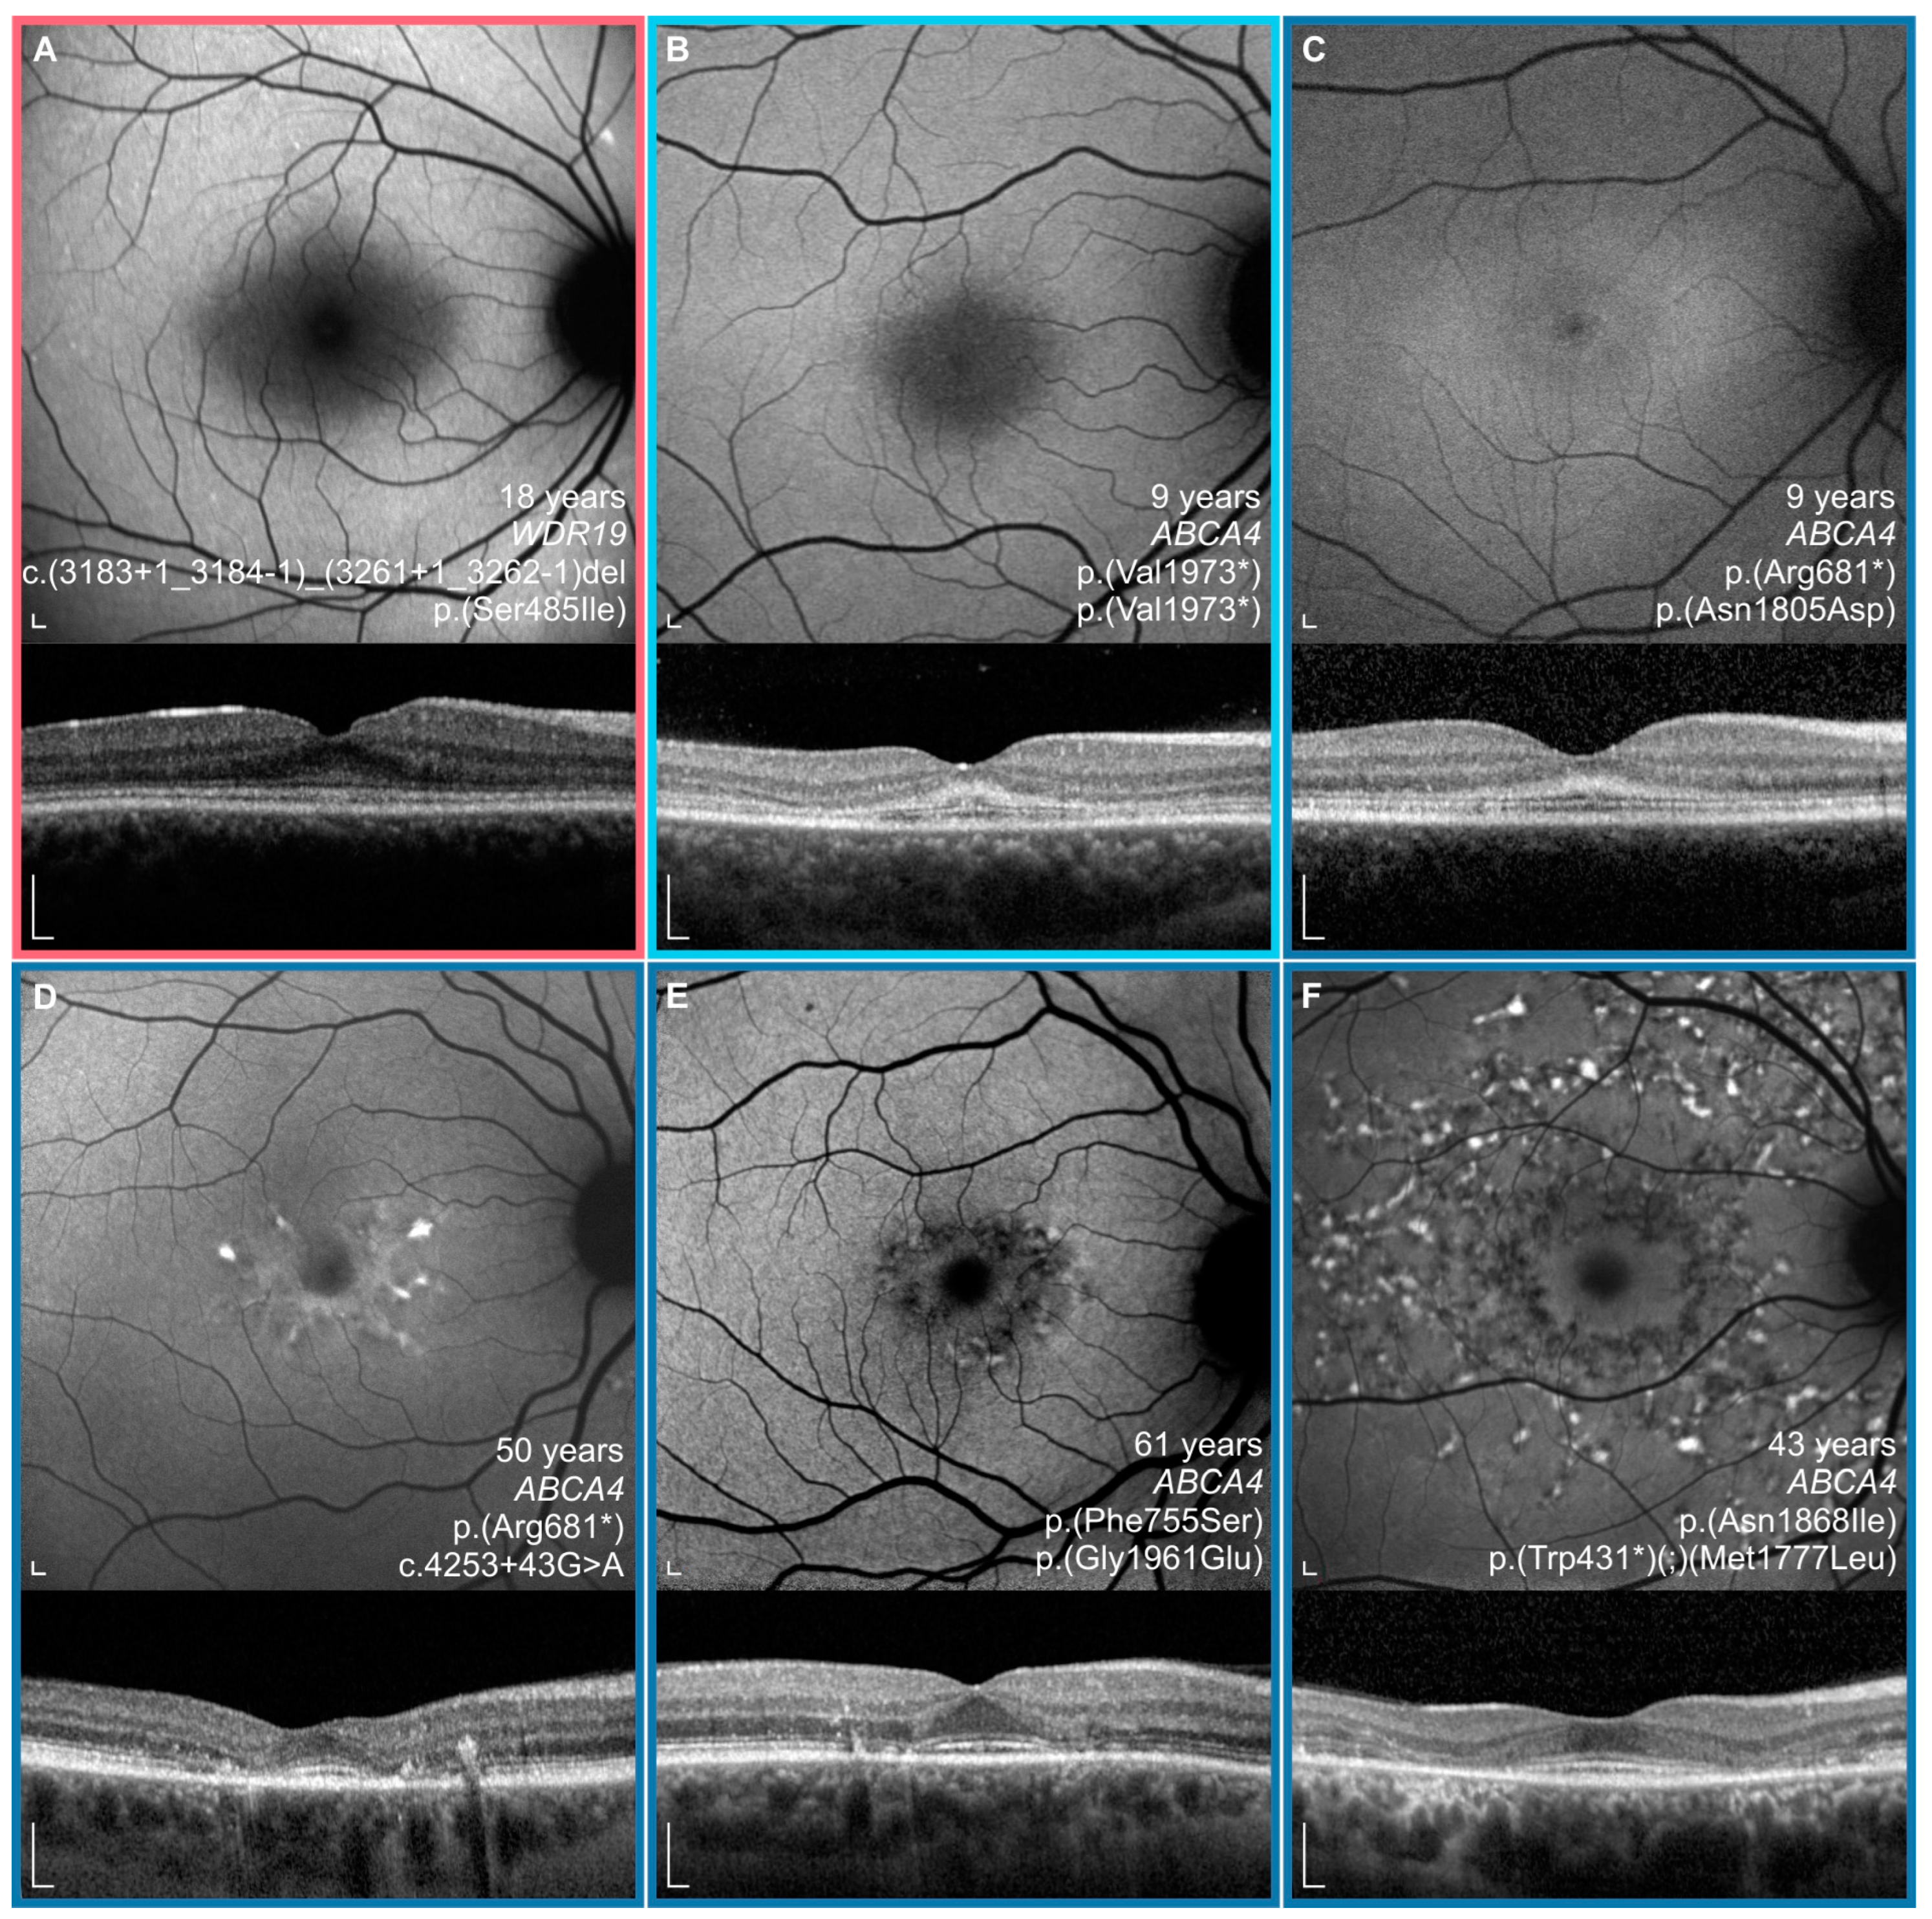

3.4. Comparison between WDR19 and ABCA4 Stargardt Patients